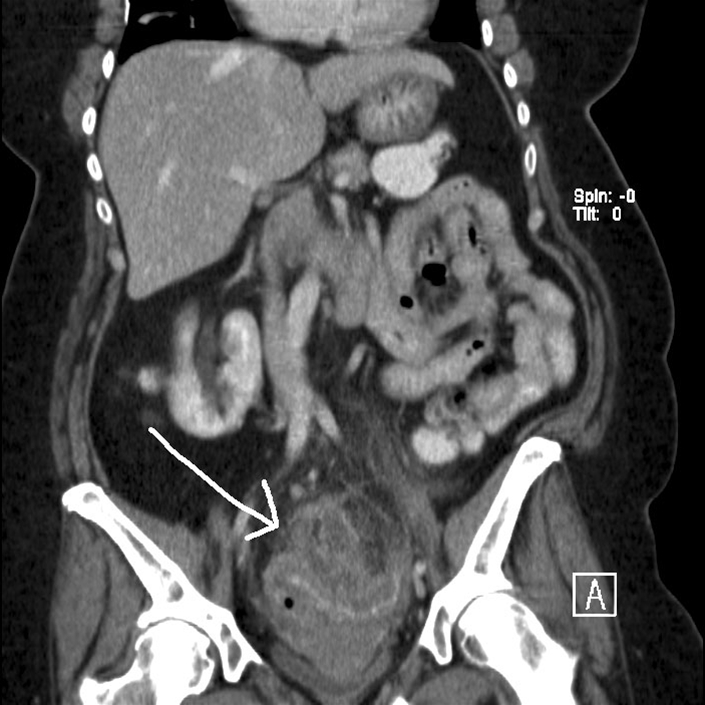

Der unverdaulichen und unverträglichen nahrungsreste. Maskformiga bihanget · blindtarm · colon (colon ascendens, höger colonflexur, colon transversum, vänster colonflexur, colon descendens, colon sigmoideum) · fortsättning (taenia coli, haustra, appendices epiploicae) Colon sigmoideum der übergang vom colon ascendens zum colon transversum ist durch eine krümmung, die flexura coli dextra , markiert. This part of the colon normally lies within the pelvis, but due to its freedom of movement it is liable to be displ. Når den nederste del af tarmen er fuld, udløses en tømningsrefleks, der meddeler hjernen, at tarmen trænger til at blive tømt.

Colon sigmoideum) — конечная часть ободочной кишки, (являющейся, в свою очередь, предпоследним отделом толстой кишки), продолжение нисходящей ободочной кишки. Zstępnica biegnie w dół i przechodzi w esicę (colon sigmoideum) w kształcie pionowej litery s. This part of the colon normally lies within the pelvis, but due to its freedom of movement it is liable to be displ. Når den nederste del af tarmen er fuld, udløses en tømningsrefleks, der meddeler hjernen, at tarmen trænger til at blive tømt. Maskformiga bihanget · blindtarm · colon (colon ascendens, höger colonflexur, colon transversum, vänster colonflexur, colon descendens, colon sigmoideum) · fortsättning (taenia coli, haustra, appendices epiploicae)